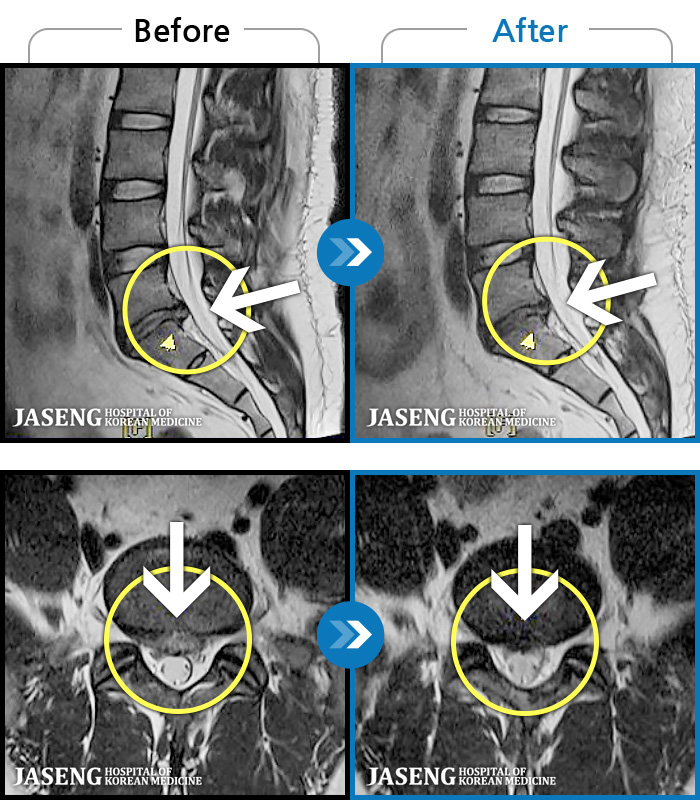

MRI ġ

1,237 MRI ũ ʸ Ȯϼ.